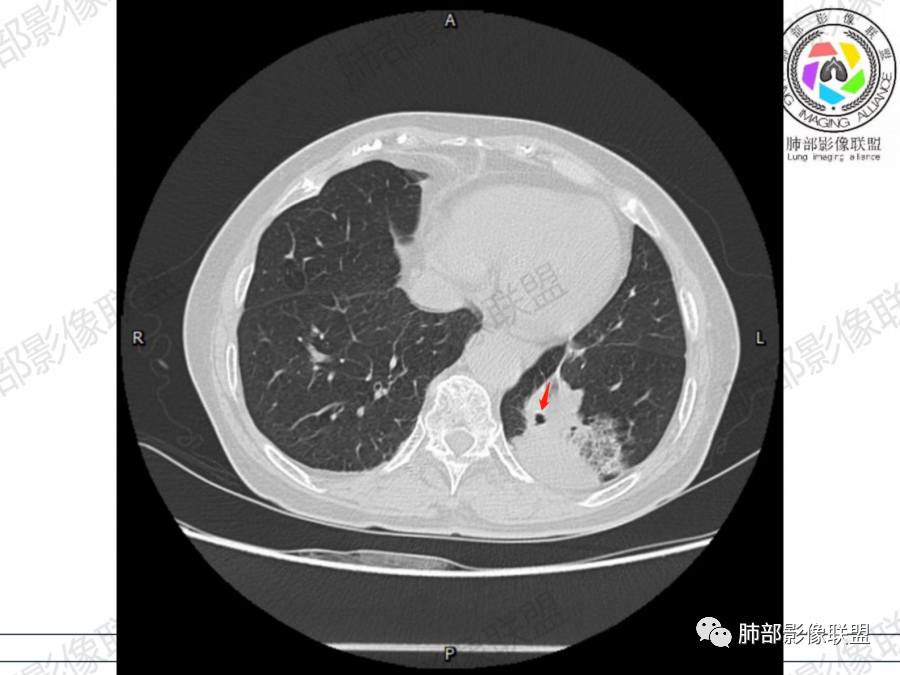

左肺下叶胸膜下混合磨玻璃影,磨玻璃边界清晰,支气管进入后堵塞,增强轻中度强化,无明显坏死空洞。

空腔+铺路石征+边界清楚GGO+病灶内血管局部扭曲+强化不均匀+病史长,指向腺癌,特别是粘液腺癌

晨读:左肺下叶胸膜下实性高密度影,部分伴有网格样增厚,内部可见小空泡,壁光滑,周围伴有磨玻璃影,边界清,近端可见支气管穿行,远端支气管堵塞,胸膜下脂肪间隙可见,病变整体收缩,部分有彭隆,增强后可见血管穿行,强化尚均匀。

周围GGO,呈碎石路征,边界清楚

主体病灶

2、影像表现:无肺气肿背景,病变定位于左肺下叶背内侧基底段,病灶呈不规则团块影,靠近胸膜侧,其内密度不均匀,内见空洞、实变及磨玻璃影,磨玻璃影呈碎石路征,边界清楚,实性肿块边界膨隆,其内见空洞。空洞周围比较实。病灶较大的支气管通畅,细小的支气管成“枯枝征”。无胸膜增厚及胸膜腔积液,增强扫描呈中度强化,见血管造影征。